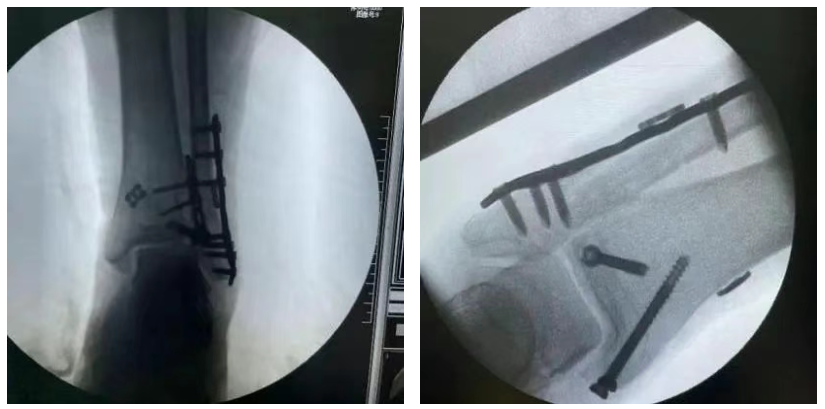

彈性固(gu)定方案(an)

手術優勢(shi):

彈性固定,強度高(gao),降低斷裂概率(lv),更(geng)少并(bing)發癥

允許病(bing)人(ren)更早的(de)進行非限制(zhi)性負重和(he)功能(neng)鍛(duan)煉

無(wu)需盡(jin)快二次取出(chu)

可調袢

型號:EBA0322

規格:12×4×1.5mm

蝶(die)形板

型號:EBA0720

規格:14×1.5mm